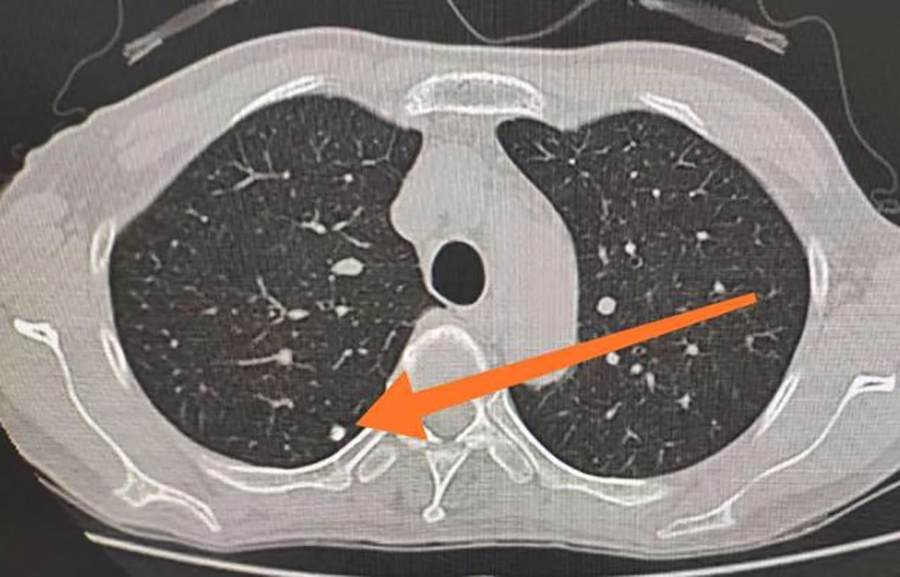

肺结节意味着得了肺癌吗?要做手术吗?同样的问题也困扰着40岁出头的李先生。一次体检中,李先生被查出双肺肺实性结节,最大的约6mm,这着实把他吓了一跳。因为不了解肺结节,让他产生了紧张、恐慌、焦虑情绪。于是,他便来到了色情片 平阳部肺病科就医。平阳部肺病科副主任王丽娜说,肺结节是影像学表现为直径≤3cm大小,局灶性、类圆形、密度高的阴影,通常不会引起临床症状,起病隐匿、不易发现,是近年来的常见病。其中,直径≤1cm时通常被描述为小结节,而直径≤0.5cm时被称为微小结节。除了大小以外,还根据结节的密度不同分为纯磨玻璃结节、部分实性磨玻璃结节和纯实性结节。

王丽娜说,临床上初次发现的肺部结节多数为良性病变。良性结节大多数是肺结核或者肺部炎症,经过治疗之后,局部组织形成瘢痕性的修复,从而表现为结节。但是,其中仍有一定比例为恶性肿瘤早期表现,比如伴有分叶、毛刺、胸膜凹陷征、支气管截断征、支气管充气征、血管集束征等变现,则考虑恶性病变的可能性较大。所以,在确诊为肺部结节后,大家也无需过度恐慌,一定要遵医嘱定期复查肺CT,以明确结节有无增长以及形态变化等问题。